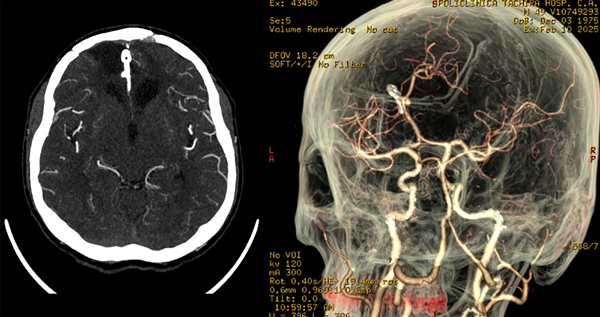

Posteriormente es trasladado a terapia intensiva intubado donde se mantiene bajo sedoanalgesia en infusión por 24 horas y, tras reversión, se evidencia Glasgow 11/15 (respuesta verbal: 4, respuesta motora: 6), sin déficit neurológico aparente. Se retira drenaje subcutáneo a las 48 horas postoperatorias. Se indica tomografía cerebral simple (Figura 3) con buen control de evacuación de las colecciones hemáticas, y la AngioTC con correcta exclusión del aneurisma (Figura 4). El paciente tiene una óptima evolución.

Figura 3. Tomografía cerebral simple. En cortes axial, coronal y sagital se muestra: cuerpo hiperdenso en fisura interhemisférica que genera discreto efecto Hounsfield correspondiente con clip simple de palas rectas normoposicionado. Áreas de encefalomalacia bifrontal. Cisternas de la base libres y permeables, sistema ventricular de topografía normal, preservación de los elementos de la línea media, presencia de surcos y circunvoluciones, adecuada diferenciación sustancia gris-blanca y corticosubcortical. Defecto de craneotomía.

Figura 4. Angiotomografía cerebral. En corte contrastado axial se observa: cuerpo hiperdenso en fisura interhemisférica que genera discreto efecto Hounsfield correspondiente con clip simple de palas rectas normoposicionado, área de encefalomalacia orbitofrontal de predominio izquierdo. En reconstrucción 3D: exclusión de la circulación de aneurisma de ACAa, clip normoposicionado, preservación de ramos vasculares distales.